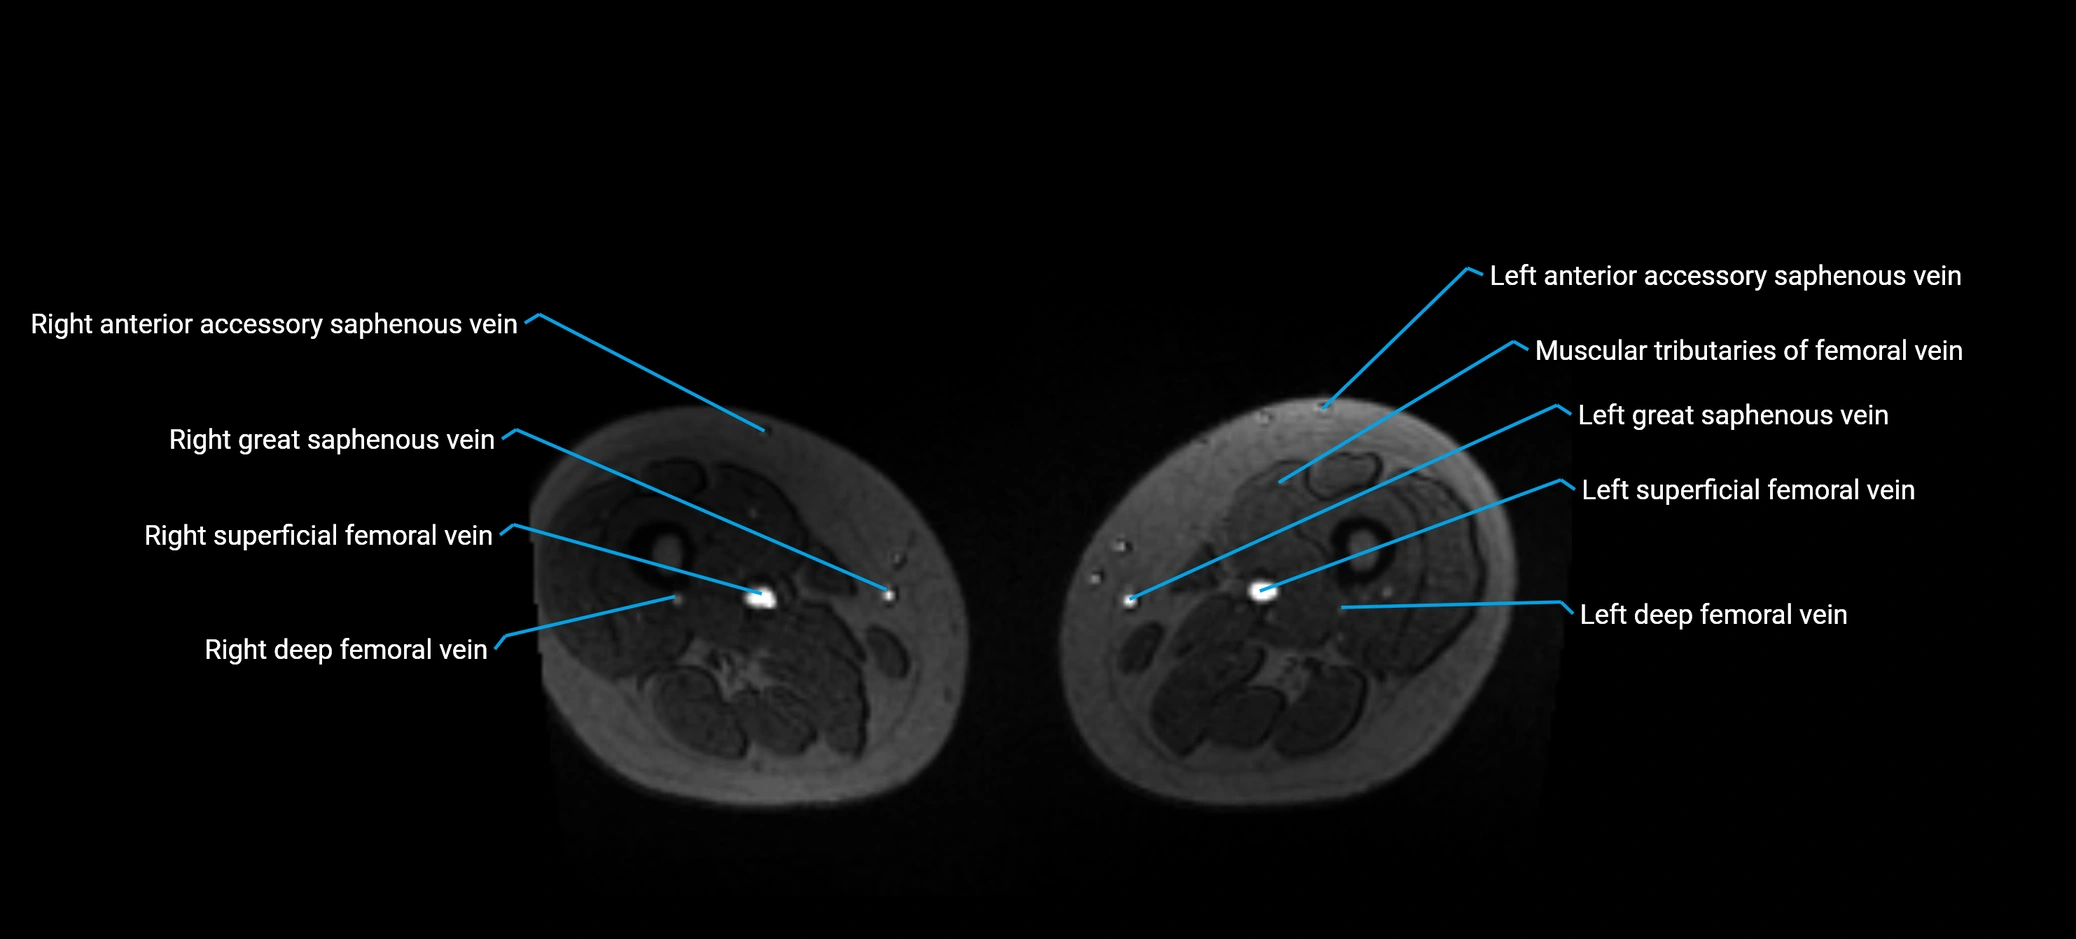

MRI image

image